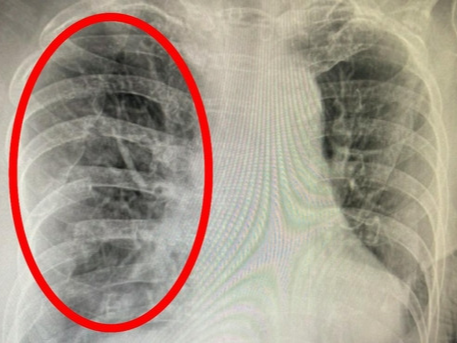

- 숨 쉴 때 심해지는 통증: 폐나 흉막 관련 문제 가능성